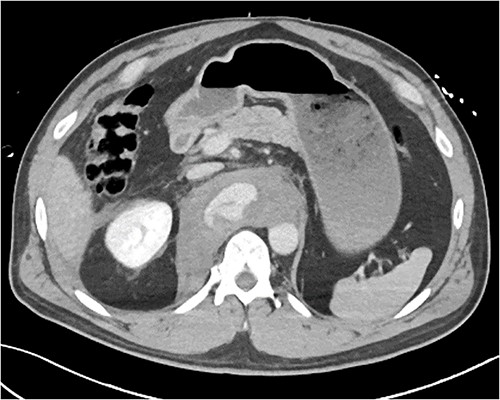

A 54-year-old male presented to our Level 1 Trauma Centre following a high-speed motor vehicle accident with rollover. Although initially haemodynamically stable, significant hypoxia prompted a trauma call activation. On arrival to the Trauma Centre, he had a Glasgow Coma Scale of 8 with an initial heart rate of 70 bpm and systolic blood pressure of 101 mmHg. A brief loss of cardiac output resulted in intubation, bilateral finger thoracostomies and the commencement of massive transfusion. Although his abdominal eFAST was positive, he was fluid responsive and proceeded to imaging. A full computed tomography (CT) trauma series demonstrated CA avulsion (Fig. 1) with contrast extravasation into the retroperitoneum and a large retroperitoneal haematoma measuring 18 cm by 9 cm (Figs 2 and 3). Nil visceral injury was identified and imaging otherwise revealed fractures of the left scapula, right 12th rib and bilateral acetabula and pubic rami.

Axial CT slice demonstrating coeliac trunk avulsion with active bleeding into a large retroperitoneal haematoma.